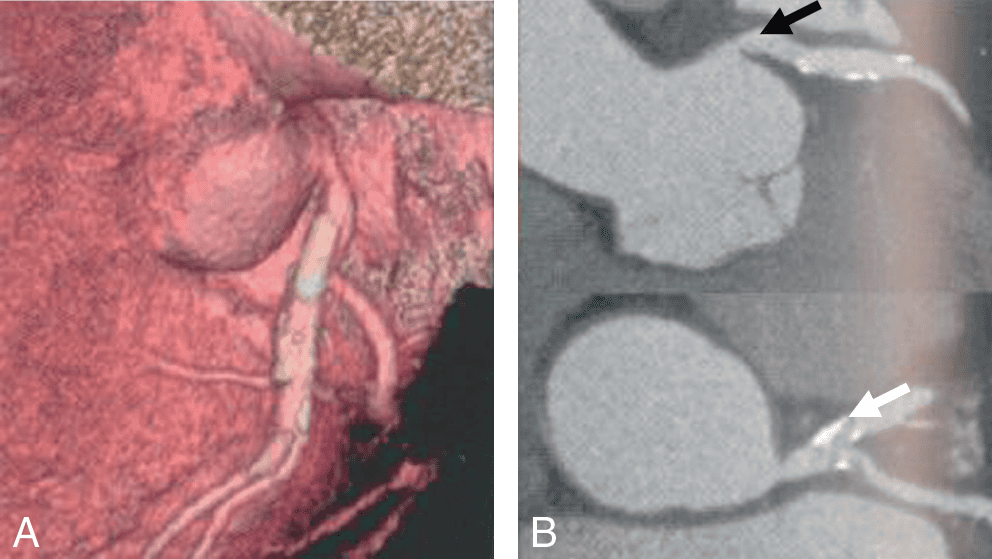

CARDIOLOGIE PÉDIATRIQUE 📌 À LA UNE : Cardiac evaluation of paediatric athletes: A clinical [...]